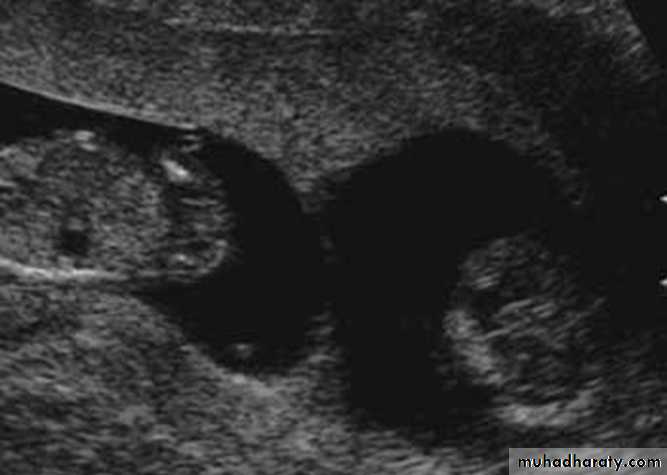

Multiple pregnancy

DefinitionsIn general terms, multiple pregnancies consist of two or more fetuses.

Twins

Classification

• number of fertilized eggs: zygosity

• number of placentae: chorionicity

• number of amniotic cavities: amnionicity.